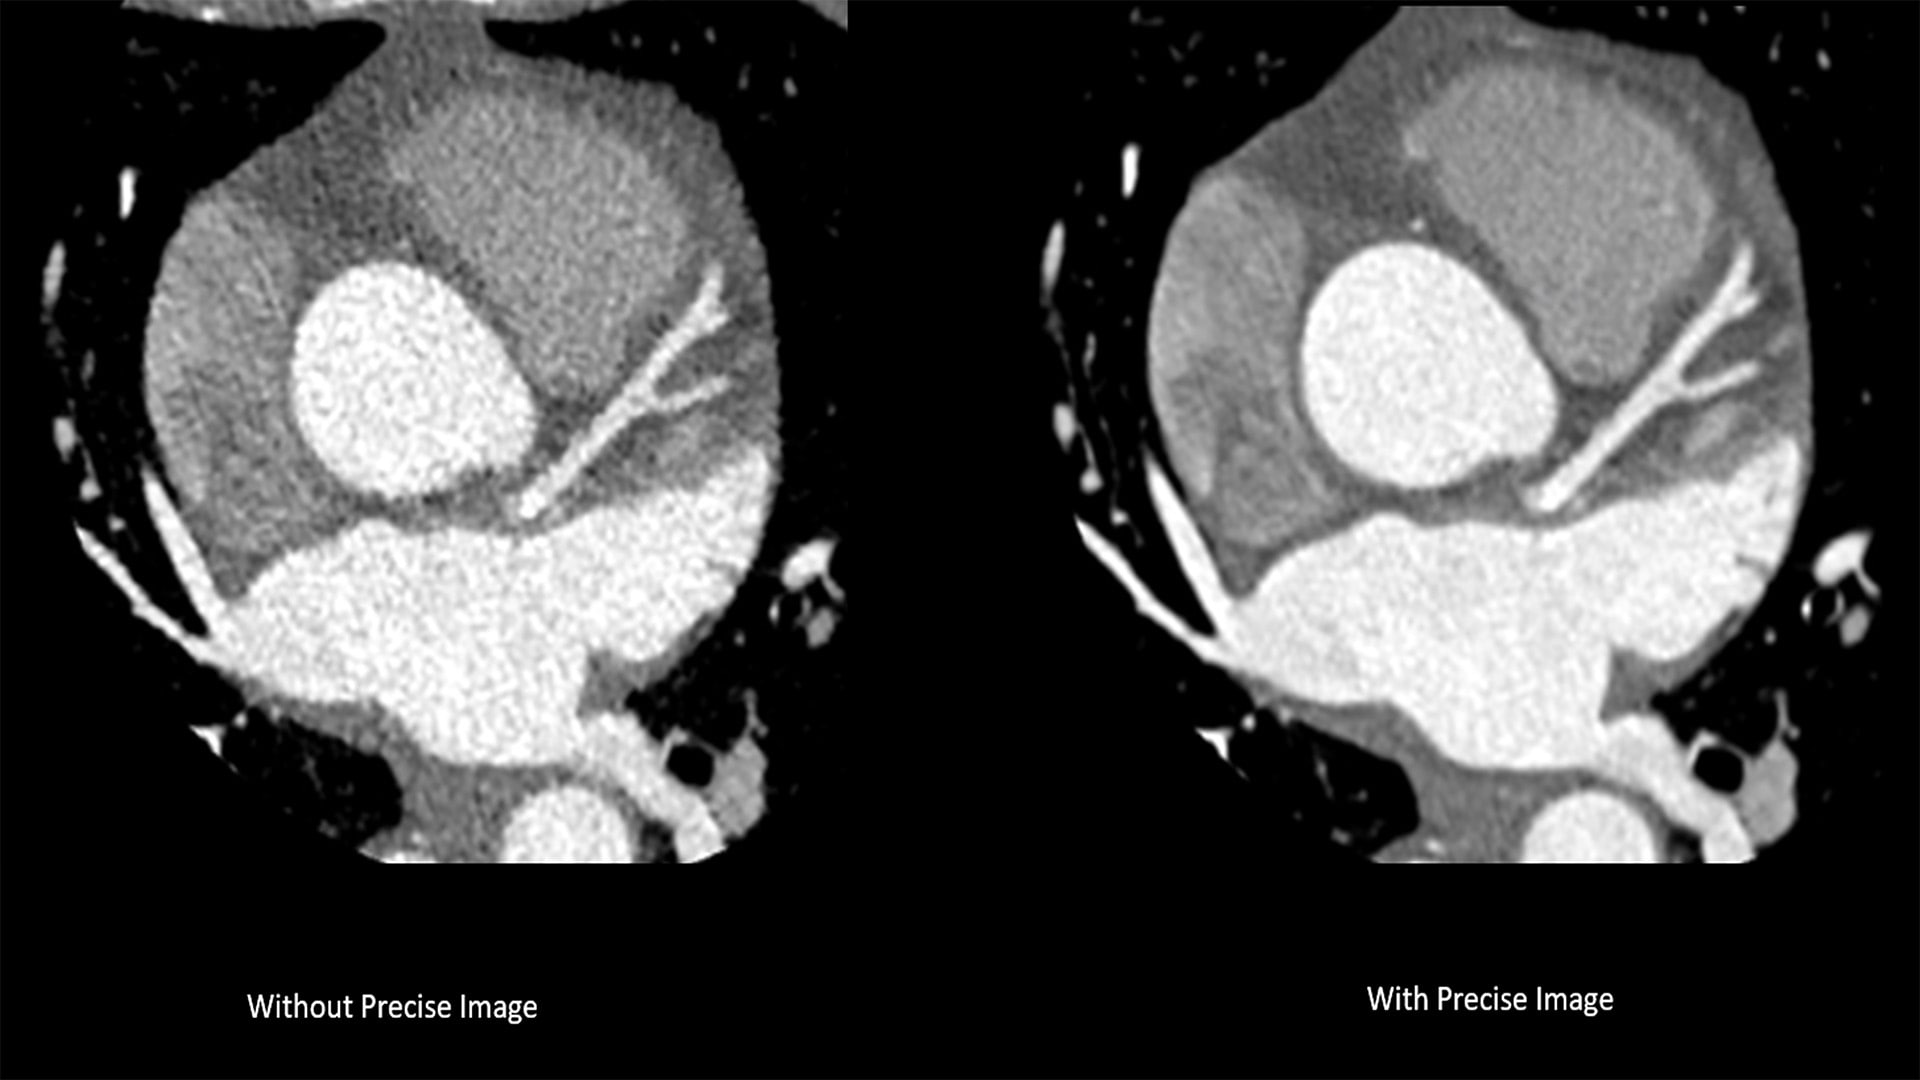

The new CT 5300 system is already installed at several European hospitals and has been well-received. “CT 5300 offers CT imaging from head to toe, combined with high-end functionality such as coronary angiography, delivering an extremely broad spectrum of applications, helping us to better manage increased volumes of patients,” said Dr. Hilmar Kühl, Head of Radiology at St. Bernhard-Hospital Kamp-Lintfort, Germany. “With this latest system from Philips, we see an improvement in image quality with Precise Imaging, and for the first time, we can now visualize cardiac anatomy by using Precise Cardiac nearly artifact-free, which is very valuable to help improve cardiac care for our patients.”

The new system introduces Nanopanel Precise, the industry’s first detector built from the ground up specifically for AI-based reconstruction. This brand-new detector leverages the full capabilities of Philips Precise Image reconstruction software to deliver high-quality images at much lower radiation dose. At 80% lower dose, Precise Image achieves up to 85% lower noise and 60% better low-contrast detectability than conventional image reconstruction [2]. Combined with Precise Cardiac motion compensation, Precise Image makes the CT 5300 particularly suitable for high-quality, motion-free, cardiac imaging [3] in patients with high heart rates or heart-rate variability.